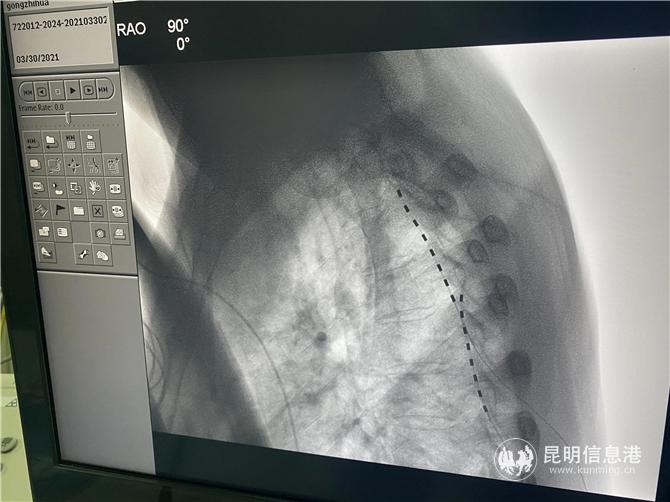

3月31日,在多学科团队的配合下,龚会军在介入杂交手术室、用局麻下为患者植入电极,由于患者之前的陈旧性损伤,患者的脊柱结构黏黏严重,给上行穿刺造成了极大的困难,同时,术中患者的疼痛位置又发生了变化,龚会军团队及时调整,术中测试患者疼痛区域全覆盖。术后,龚志华的疼痛明显缓解。(6686体育 记者孙红亮)